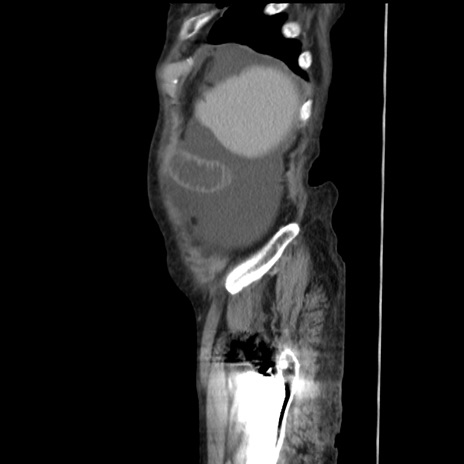

症例31(矢状断像)

【症例】80歳代 女性

【主訴】腹部膨満感

【現病歴】他院にて肝硬変にてフォロー中。1週間前から便秘、腹部膨満感、臍部腫瘤あり受診となる。

【既往歴】肝硬変

【身体所見】腹部膨隆あり、皮膚変化なし、疼痛なし。

【データ】WBC 4600、CRP 0.25